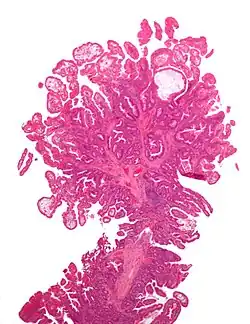

Adenomatous colon polyp with malignant focus at apex

Colorectal adenocarcinoma 100%

• In carcinoma in situ (Tis): cancer cells invading into the lamina propria, and may involve but not penetrate the muscularis mucosae. Can be classified as "high-grade dysplasia", because prognosis and management are essentially the same.[10]

• Invasive adenocarcinoma: Extending through the muscularis mucosae into the submucosa and beyond.[10]